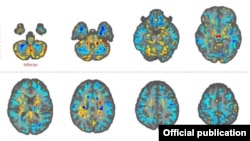

Las imágenes revelaron “diferencias significativas en el volumen de materia blanca cerebral total, [en] volúmenes locales de materia blanca y gris”, y en la integridad microestructural del tejido del cerebelo. También mostraron diferencias de “conectividad en las subredes auditivas y visoespaciales, pero no en la subred de control ejecutivo”.

“Lo que pueden decirnos las imágenes cerebrales [de resonancia magnética] es si le pasó algo al cerebro”, le dijo a The New York Times la doctora Ragini Verma, profesora de Radiología de la Universidad de Pensilvania y la encargada del estudio. “Y la respuesta es que sí […], pero no sé la causa. Las imágenes por sí mismas no pueden decirnos eso”.

En declaraciones al periódico británico The Guardian, Verma observa que los resultados de la investigación son desconcertantes, porque los cerebros de los diplomáticos mostraron lo contrario de lo que comúnmente aparece cuando hay daño cerebral.

En vez de dilatarse, la región llamada vermis –que ayuda a coordinar los movimientos del tronco y de las extremidades y maneja señales visuales y auditivas-- se contrajo, y lejos de disminuir, un factor de análisis clínico llamado anisotropía fraccional aumentó.